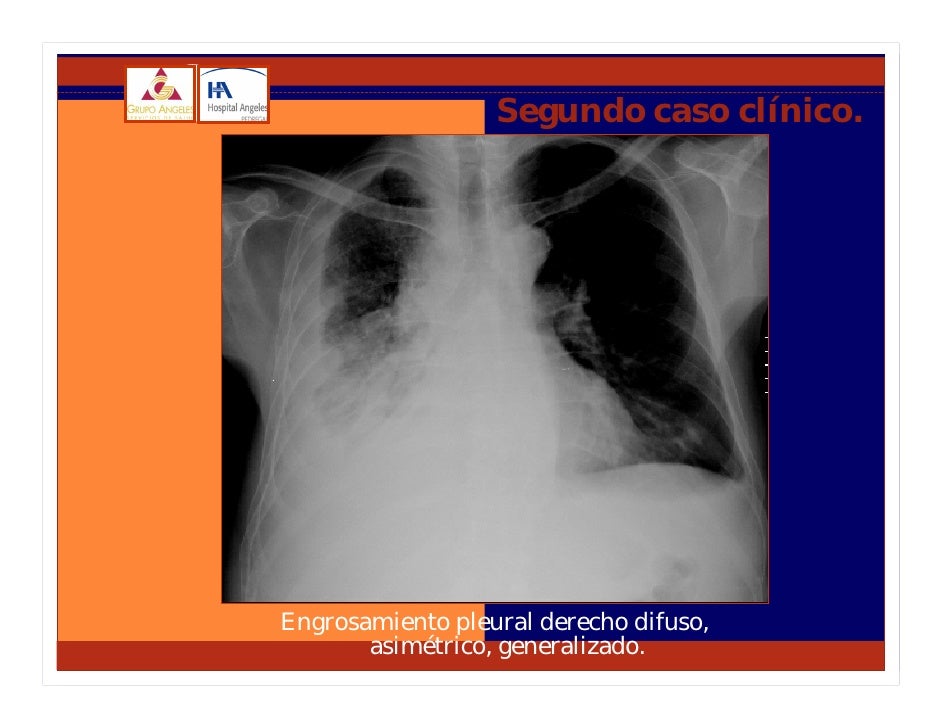

Tumoral cd10 expression correlates with aggressive histology. Presently, tumornodemetastasis level and histologic type are the established prognostic factors for malignant pleural mesothelioma, whereas no prognostic markers. Most cancers wikipedia. Most cancers; synonyms malignant tumor, malignant neoplasm a coronal ct experiment displaying a malignant mesothelioma legend → tumor ←, important pleural effusion, 1 & three lungs. Mesothelioma wikipedia. Symptoms and signs pleural mesothelioma. Symptoms or symptoms of mesothelioma won't appear until 20 to 50 years (or greater) after publicity to asbestos. Mesothelioma is a sort of cancer that develops from the skinny layer of tissue that covers among the inner organs. The most not unusual place affected is the liner of the lungs and chest wall. En.Wikipedia. The iaslc lung most cancers staging task proposals for. The iaslc lung cancer staging mission proposals for revision of the tnm stage groupings in the imminent (8th) version of the tnm type for lung cancer.